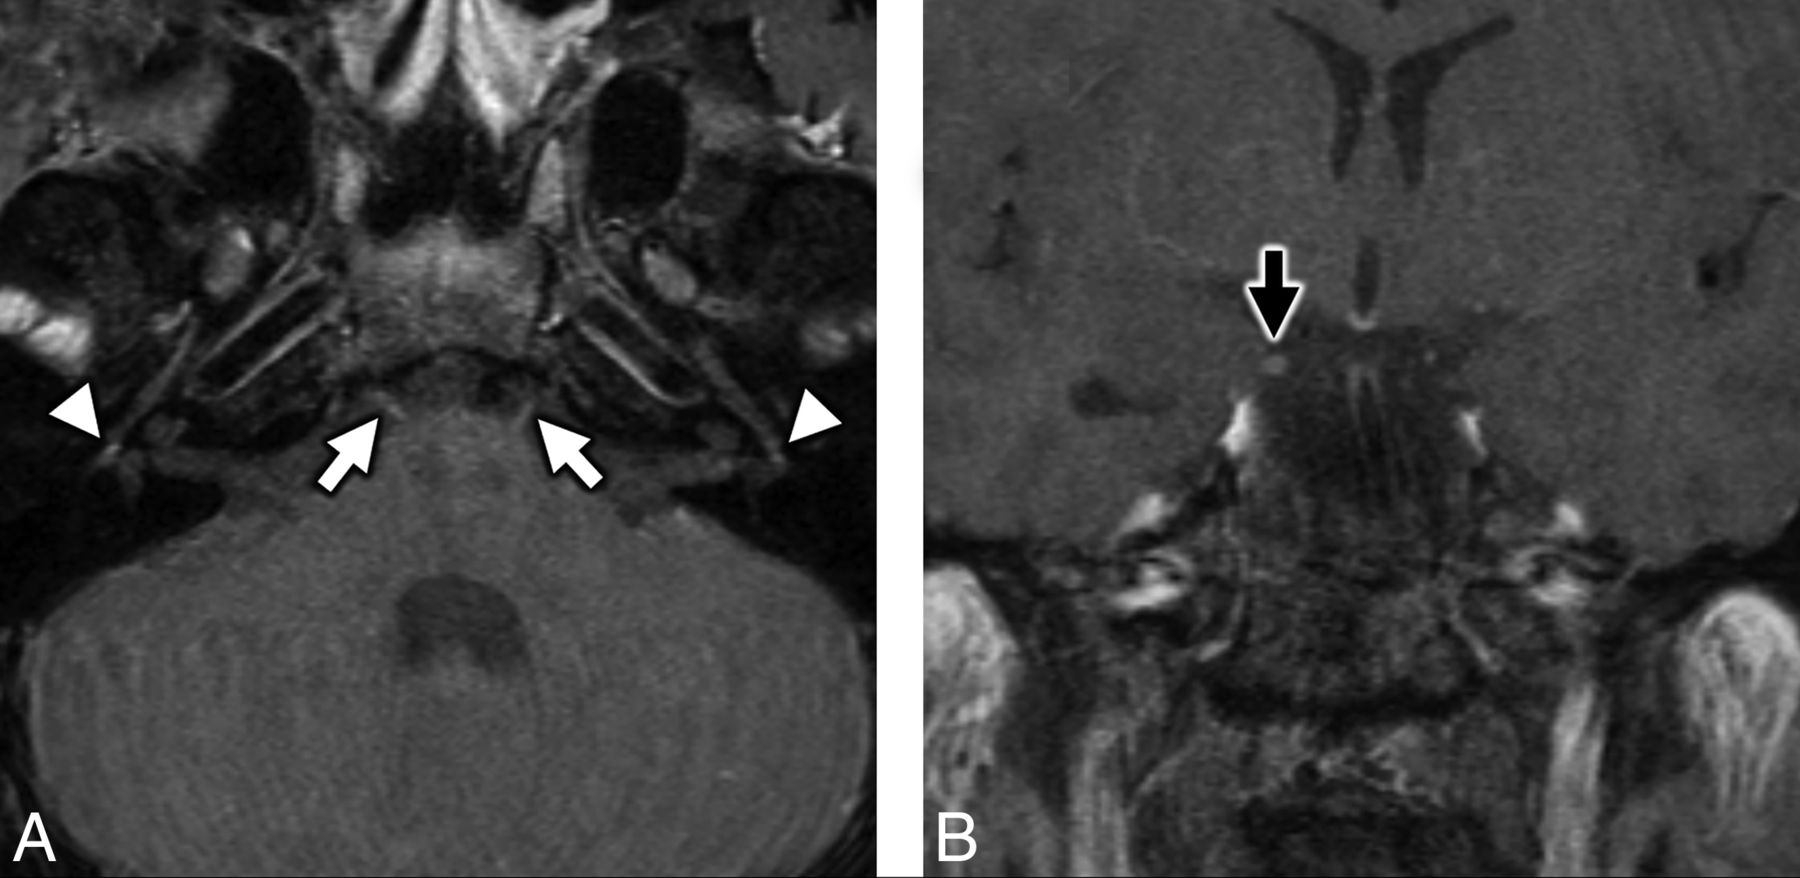

MR imaging of the temporal bones in a patient with antecedent COVID-19 and new-onset bifacial weakness and paresthesia subtype Guillain-Barré syndrome. Axial postcontrast T1-weighted fat-saturated MR imaging of the temporal bones (A) shows subtle-but-abnormal enhancement along the cisternal segments of the abducens nerves (CNVI) bilaterally (white arrows), as well as subtle enhancement along the tympanic segments of the intratemporal facial nerves (CNVII) bilaterally (white arrowheads). Coronal postcontrast T1-weighted fat-saturated MR imaging (B) shows subtle asymmetric enhancement along the cisternal segment of the right oculomotor nerve (CNIII, black arrow).

MRI of the brain in a patient with antecedent COVID-19 and new onset bifacial weakness and paresthesias subtype Guillain-Barré syndrome. Axial post-contrast T1-weighted SPoiled Gradient-Recalled (SPGR) MRI shows abnormal enhancement of the right oculomotor nerve (CNIII, white arrow, A), the cisternal segments of the abducens nerves (CNVI) bilaterally (white arrowheads, B), the distal canalicular segments of the facial nerves (CNVII) bilaterally (black arrows, C), and the proximal tympanic segments of the intratemporal facial nerves (CNVII) bilaterally (black arrowheads, C).